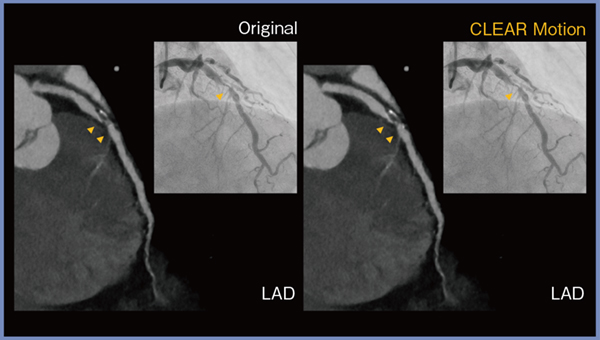

冠動脈での症例を提示する。冠動脈カテーテル検査を施行した際に,心拍はそれほど速くないにもかかわらず,右冠動脈の中心部あたりの動きが大きく,画像にブレが生じる例を時に経験する。図5は,オリジナル画像ではやや不明瞭な左前下行枝(LAD)の病変(▶)が,CLEAR Motionによって明瞭となっており,短軸像ではCLEAR Motion による描出の改善がより顕著であった。

図5 CLEAR Motionによる冠動脈の描出の改善(長軸像)